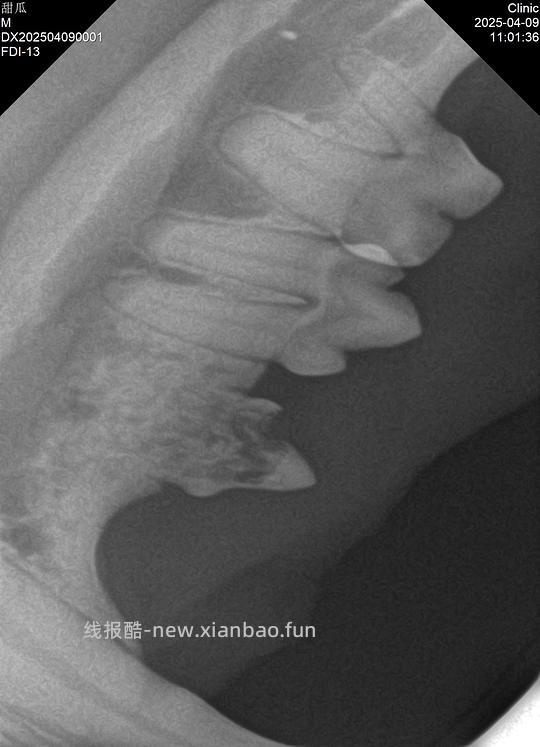

Type1可能和牙周病相关(好好刷牙对1型还是有帮助的),完整拔牙;Type2特应性,原因未知,甜瓜407号牙就是2型,牙冠切除;Type3是T1+T2,手术方案由医生评估,甜瓜307号牙是3型,完整拔除。

牙吸收无法阻止也无法预测,这意味着拔除病变牙后其他牙未必一定会吸收。所以我选择听医生的专业意见,处理影像学中确认牙吸收的坏牙307和407(这两颗牙通常是牙吸收最先发生的位置),因为106、206的牙龈也有红肿迹象,拔了也不影响咬合,虽然目前不是牙吸收,在我的要求下医生同意拔除了。309和409两颗下牙或许因为清洁不到位,有不同程度的早期牙周病,但只要做好维护不至于拔除,我会每天好好清洁,遵循医嘱,在甜瓜十岁前再拍一次牙片,如果牙况恶化,会根据届时情况选择合适的牙科手术方案。